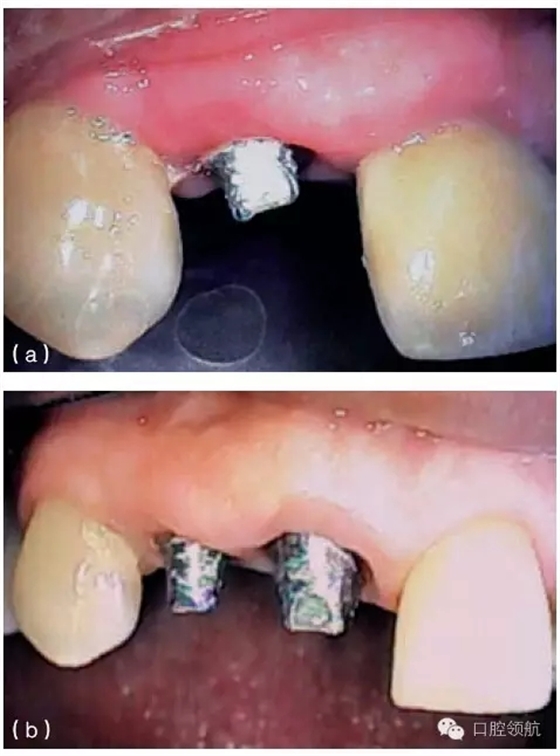

種植體周圍有一個(gè)淺的組織袖口,但這個(gè)袖口可能位于鄰近牙或種植體的根方。當(dāng)種植體植入時(shí),牙槽嵴已經(jīng)發(fā)生垂直吸收,就會(huì)出現(xiàn)這種情況。當(dāng)種植體植入這些未行位點(diǎn)恢復(fù)的區(qū)域時(shí),種植體跟鄰牙間的牙齦不在同一水平,這將造成不平整的牙齦形態(tài)。如果修復(fù)體在美學(xué)區(qū)域內(nèi),使用齦色瓷(或復(fù)合材料)可以部分遮蓋牙齦高度差異(圖9.24a,b)。另外,當(dāng)一個(gè)長(zhǎng)的臨床牙冠可以被患者的嘴唇遮蓋時(shí),這種方案也是可取的。因而,在制訂治療計(jì)劃的時(shí)期,就要考慮到是否存在不一致的骨水平。為了克服這些不一致的情況,獲得滿意的修復(fù)效果,使用CT檢查及外科模板,有利于評(píng)估預(yù)期修復(fù)體與缺失軟硬組織之間的

關(guān)系。如果這些不規(guī)則的差異,在美學(xué)方面不能讓患者滿意,醫(yī)生在診斷和進(jìn)行外科手術(shù)之前,必須充分評(píng)估及討論缺失組織的再生潛力。

圖9.24 (a) 由于種植體植入前,沒有進(jìn)行充分的位點(diǎn)恢復(fù),最終在修復(fù)體唇面輔以齦色瓷,以彌補(bǔ)軟組織的不足。(b)口內(nèi)全景觀,全口烤瓷熔附金屬修復(fù)體,粘結(jié)固位,注意左側(cè)側(cè)切牙牙齦區(qū)域的齦色瓷。